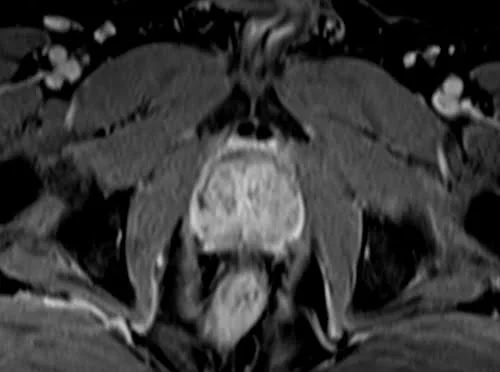

VIBE FAT SAT AXIAL POST CONTRAST SEQUENCE USED IN PROSTATE IMAGING